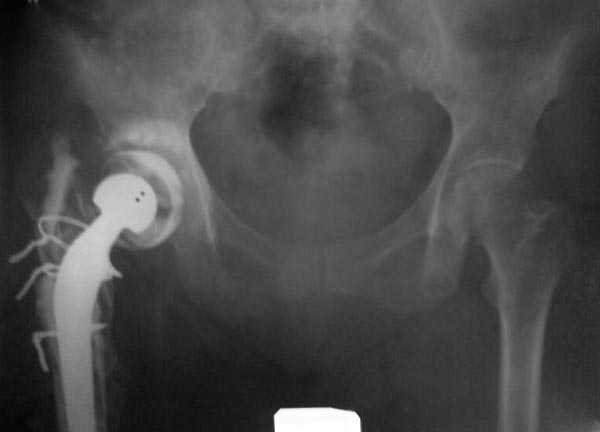

Вот снимки по свежей ситуации, парень 19 лет, длинный оскольчатый перелом бедра от шейки до в-с/3. давно уже ходит на своих ногах.

Делалось не мной (ассистировал), я на тазах "пока ещё не волшебник, а только учусь"

Представленные Вами рентгенограммы действительно являются примером качественной фиксации спице-стержневым аппаратом. Они, как ни что другое, многое иллюстрируют.

Кроме того, было бы ошибкой ставить знак равенства между нашим и Вашим пациентами. Они не только не похожи, разница между ними просто огромная. Говорю это не для того, чтобы задеть Вас или обидеть. Ни в коем случае. Просто теперь я понимаю, что Ваше мнением строится на простом преломлении Ваших подходов к лечению пациентов со свежими переломами, на ситуацию, абсолютно несопоставимую, подобную нашей.